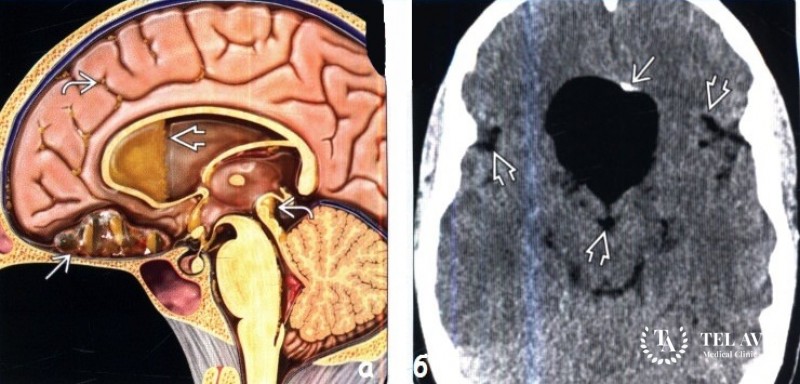

Дермоидная киста – является доброкачественным образованием, которое имеет вид мешочка, а по строению напоминает кожу. Зачастую врач может обнаружить опухоль на голове, спине или половых органах. Такое образование может включать в себя сальные и потовые железы, кожу и костную ткань. С течением времени опухоль может преобразоваться в злокачественную и начать сдавливать соседние ткани и структуры. Врач, который обнаружил данное заболевание, приступает к немедленному его лечению.